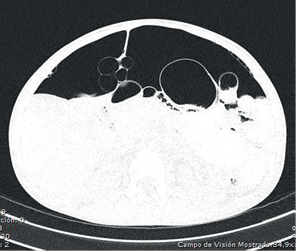

Al no encontrarse signos de irritación peritoneal, se practicó una tomografía toraco-abdominal en la que se observó: derrame pleural bilateral con engrosamiento de las cisuras, bronquiectasias basales bilaterales, atelectasia parcial de ambos lóbulos inferiores, notoria distensión del esófago con sonda en su interior, hidroneumoperitoneo, abundante líquido libre en la cavidad abdominal y distensión de las asas intestinales (figuras 1,2,3).

Figura 2. Tomografía computarizada de abdomen simple y con contraste, en las que se observa neumoperitoneo y líquido libre en la cavidad peritoneal.